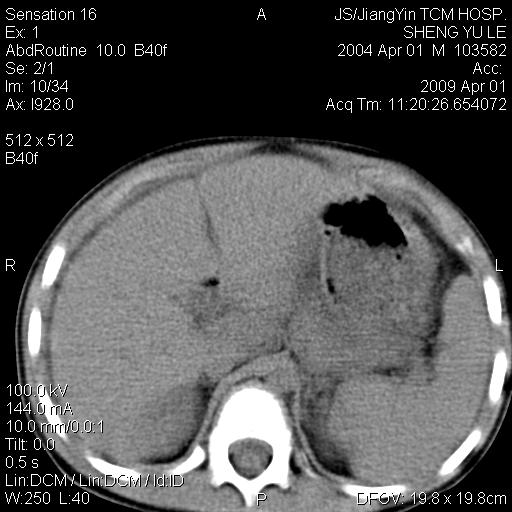

m,5岁。尿痛尿频数天。既往无病史。ct平扫腹盆腔积液。膀胱壁明显增厚。另可见心包增厚。wbc5万,骨髓穿等结果。请指教。

膀胱影像表现结合临床应该是急性膀胱炎症,但为什么有腹水呢?双肾输尿管无扩张,泌尿系压力应该不大不至于引起尿外渗,应该是腹膜感染引起的,但楼主没有提及相关症状,腹膜及膀胱结核?患者白细胞5万(结核不至于这么高啊),脾脏增大,是不是有白血病?进一步检查。。